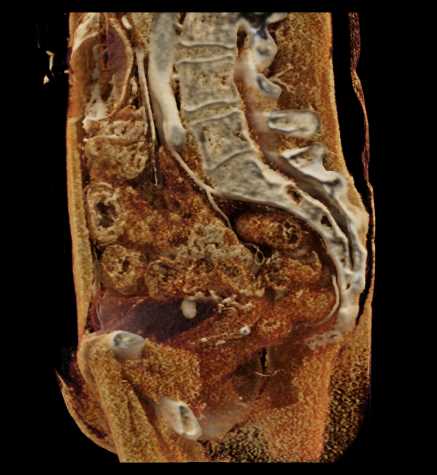

Urachal Carcinoma of the Bladder